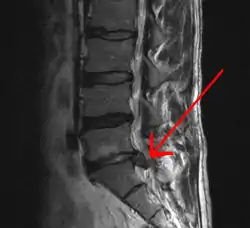

In most episodes, a specific underlying cause is not identified or even looked for, with the pain believed to be due to mechanical problems such as muscle or joint strain.[1][4] If the pain does not go away with conservative treatment or if it is accompanied by "red flags" such as unexplained weight loss, fever, or significant problems with feeling or movement, further testing may be needed to look for a serious underlying problem.[5] In most cases, imaging tools such as X-ray computed tomography are not useful and carry their own risks.[9][10] Despite this, the use of imaging in low back pain has increased.[11] Some low back pain is caused by damaged intervertebral discs, and the straight leg raise test is useful to identify this cause.[5] In those with chronic pain, the pain processing system may malfunction, causing large amounts of pain in response to non-serious events.[12]

An intervertebral disc has a gelatinous core surrounded by a fibrous ring.[34] When in its normal, uninjured state, most of the disc is not served by either the circulatory or nervous systems – blood and nerves only run to the outside of the disc.[34] Specialized cells that can survive without direct blood supply are in the inside of the disc.[34] Over time, the discs lose flexibility and the ability to absorb physical forces.[26] This decreased ability to handle physical forces increases stresses on other parts of the spine, causing the ligaments of the spine to thicken and bony growths to develop on the vertebrae.[26] As a result, there is less space through which the spinal cord and nerve roots may pass.[26] When a disc degenerates as a result of injury or disease, the makeup of a disc changes: blood vessels and nerves may grow into its interior and/or herniated disc material can push directly on a nerve root.[34] Any of these changes may result in back pain.[34]

Tests

Imaging is indicated when there are red flags, ongoing neurological symptoms that do not resolve, or ongoing or worsening pain.[5] In particular, early use of imaging (either MRI or CT) is recommended for suspected cancer, infection, or cauda equina syndrome.[5] MRI is slightly better than CT for identifying disc disease; the two technologies are equally useful for diagnosing spinal stenosis.[5] Only a few physical diagnostic tests are helpful.[5] The straight leg raise test is almost always positive in those with disc herniation.[5] Lumbar provocative discography may be useful to identify a specific disc causing pain in those with chronic high levels of low back pain.[43] Similarly, therapeutic procedures such as nerve blocks can be used to determine a specific source of pain.[5] Some evidence supports the use of facet joint injections, transforminal epidural injections and sacroilliac injections as diagnostic tests.[5] Most other physical tests, such as evaluating for scoliosis, muscle weakness or wasting, and impaired reflexes, are of little use.[5]

Complaints of low back pain are one of the most common reasons people visit doctors.[9][44] For pain that has lasted only a few weeks, the pain is likely to subside on its own.[45] Thus, if a person's medical history and physical examination do not suggest a specific disease as the cause, medical societies advise against imaging tests such as X-rays, CT scans, and MRIs.[44] Individuals may want such tests but, unless red flags are present,[10][46] they are unnecessary health care.[9][45] Routine imaging increases costs, is associated with higher rates of surgery with no overall benefit,[47][48] and the radiation used may be harmful to one's health.[47] Fewer than 1% of imaging tests identify the cause of the problem.[9] Imaging may also detect harmless abnormalities, encouraging people to request further unnecessary testing or to worry.[9] Even so, MRI scans of the lumbar region increased by more than 300% among United States Medicare beneficiaries from 1994 to 2006.[11]